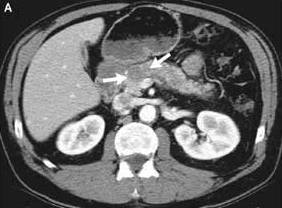

CT cancer: ab , c, d, e, f        CT of a resectable case, more CT and more CT